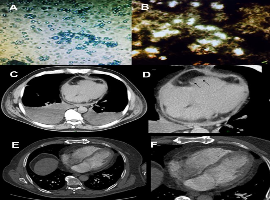

Citation: Barrera-Ramirez CF, Diaz-Castano AN, Ilarraza-Lomelí H, et al. Isolated Cardiac Cryptococcosis in an Immunocompetent Host. Clin Image Case Rep J. 2020; 2(3): 116.